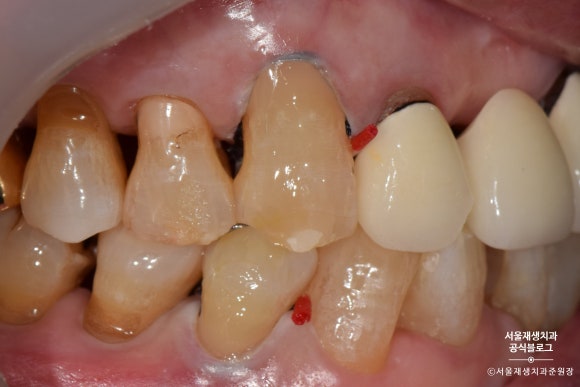

짠!

완성되었습니다.

치아와 잇몸의 경계부위를 때우기 때문에,

깔끔한 마무리를 위해 잇몸쪽으로 기구 손질을 많이 하게 됩니다.

잇몸 가장자리가 빨개진 것은 대개 하루이틀이면 원래대로 돌아옵니다.

꼼꼼한 치료의 결과라고 생각해주시면 됩니다^^

글라스아이오노머로 치경부마모증 치료하기

레진에 비해 자연스러움이나 수명은 약간 부족하지만,

저렴한 가격에

치경부마모증의 치료를 위한

최소한의 자격요건을 갖춘 기특한 재료입니다.

글라스아이오노머로 치료를 시작해보겠습니다.

며칠 후 글라스아이오노머 치료를 위해 다시 방문해주셨습니다.

그 사이 감쪽같이 아문 잇몸이 보이시나요?^^

레진과 비교했을 때 약간 혼탁한 색감, 부자연스러운 느낌은 있지만,

후방치아 치료용으로는 손색이 없습니다^^